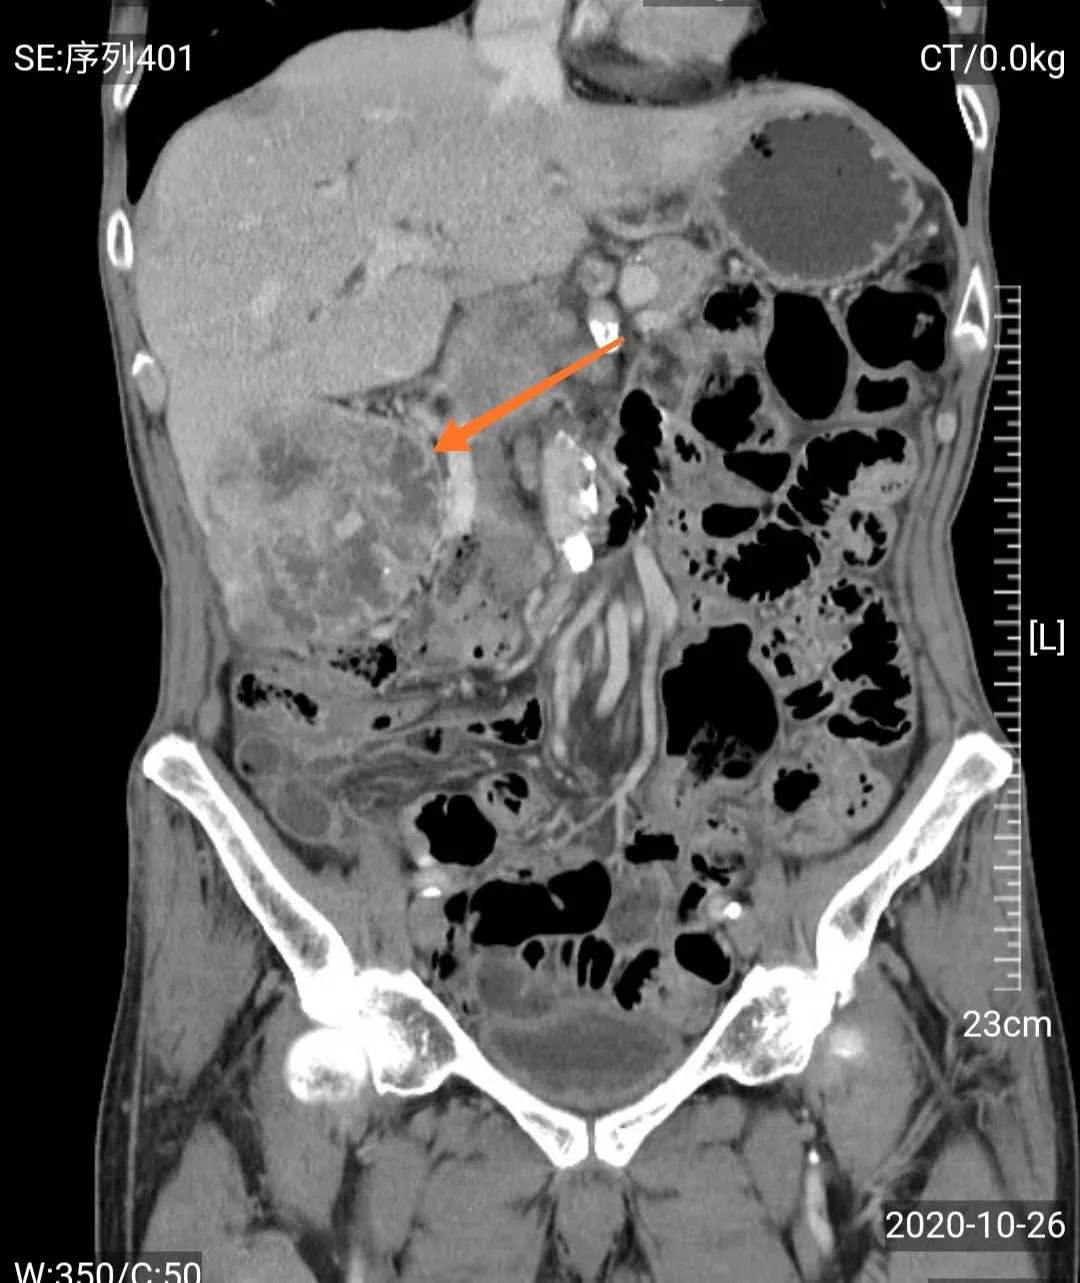

然而,门诊泌尿系超声检查发现,梁爷爷除了前列腺增生外,还有一个可怕的问题——右肾巨大肿瘤,考虑右肾癌可能性大。

经MDT团队研究,影像学团队分析认为老人诊断右肾癌相对明确,手术治疗是首选方案;心血管及肺病科团队认为老人虽然年龄大,高血压病史,但血压控制较好,心肺功能评估认为手术风险属于轻度;肿瘤科认为患者手术指征很明确,目前一般情况好,预期寿命长,内科治疗效果不及外科手术;中医治疗可以在外科手术后辅助,不能仅靠中医治疗。泌尿外科团队认为患者诊断考虑右肾癌,且左肾功能正常,右肾肿瘤巨大,建议根治性手术切除,考虑老人年纪大,开放手术创伤大,出血多,建议采用3D腹腔镜微创治疗。

如前所说的血尿,是肾癌的常见症状,而当肾癌患者发现有肉眼血尿时,表示肿瘤已经侵入肾盏、肾盂了。随着肿瘤生长,会牵拉肾包膜,或者侵犯到邻近的腰肌和器官,此时会产生腰部的疼痛,一般呈钝痛或隐痛;肾内的血块通过输尿管还会引起肾绞痛。假如是比较大的肿瘤,还可以在患者腰部或腹部触摸到肿块。血尿、疼痛、肿块称为肾癌的“三联征”,但多数患者只会出现其中之一或两项,而这时肾癌都已经发展到较晚期了。